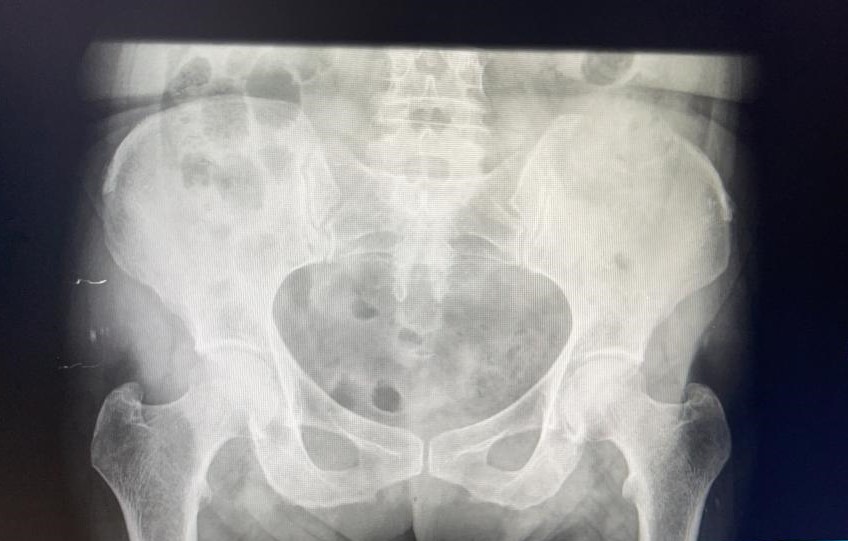

Rx pelvis: borrado de corticales en cresta ilíaca izquierda.

Se decide pedir ecografía reglada para valorar estudio posterior. Ecografía confirma sospecha de LOES intrahepáticas. Desde radiología amplian estudio con TAC: lesión ósea lítica con criterios de agresividad expansiva con masa de partes blandas en vertiente posterior de pala ilíaca izquierda.